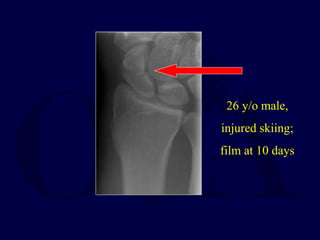

26 y/o male,

injured skiing;

film at 10 days

4 months post injury, fracture has displaced in cast

-delayed union

18 months post ORIF,

full motion, no pain,

has returned to full

activity